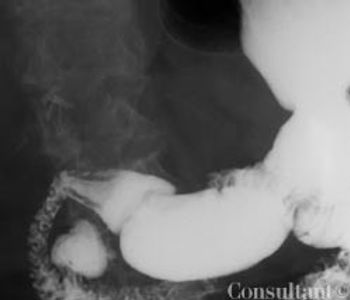

A 34-year-old white woman presentswith a 4-month history of diarrhea,with bulky, foul-smelling stools; flatulence;diffuse abdominal discomfort;and episodic nausea and vomiting. Shehas lost 13.5 kg (30 lb) during this period.The patient has had no fever, andher medical, family, and travel historyare unremarkable.